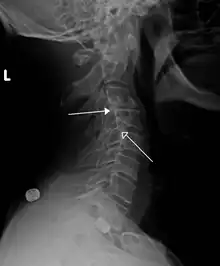

| X-ray of the lateral lumbar spine with a grade III anterolisthesis at the L5-S1 level | |

Spondylolisthesis is the displacement of one spinal vertebra compared to another. While some medical dictionaries define spondylolisthesis specifically as the forward or anterior displacement of a vertebra over the vertebra inferior to it (or the sacrum),[1][2] it is often defined in medical textbooks as displacement in any direction.[3][4] Spondylolisthesis is graded based upon the degree of slippage of one vertebral body relative to the subsequent adjacent vertebral body.[5] Spondylolisthesis is classified as one of the six major etiologies: degenerative, traumatic, dysplastic, isthmic, pathologic, or post-surgical.[6] Spondylolisthesis most commonly occurs in the lumbar spine, primarily at the L5-S1 level, with the L5 vertebral body anteriorly translating over the S1 vertebral body.[6]

Classification by degree of the slippage, as measured as percentage of the width of the vertebral body:[14] Grade I spondylolisthesis accounts for approximately 75% of all cases.[6]

- Grade I: 0–25%

- Grade II: 25–50%

- Grade III: 50–75%

- Grade IV: 75–100%

- Grade V: greater than 100%